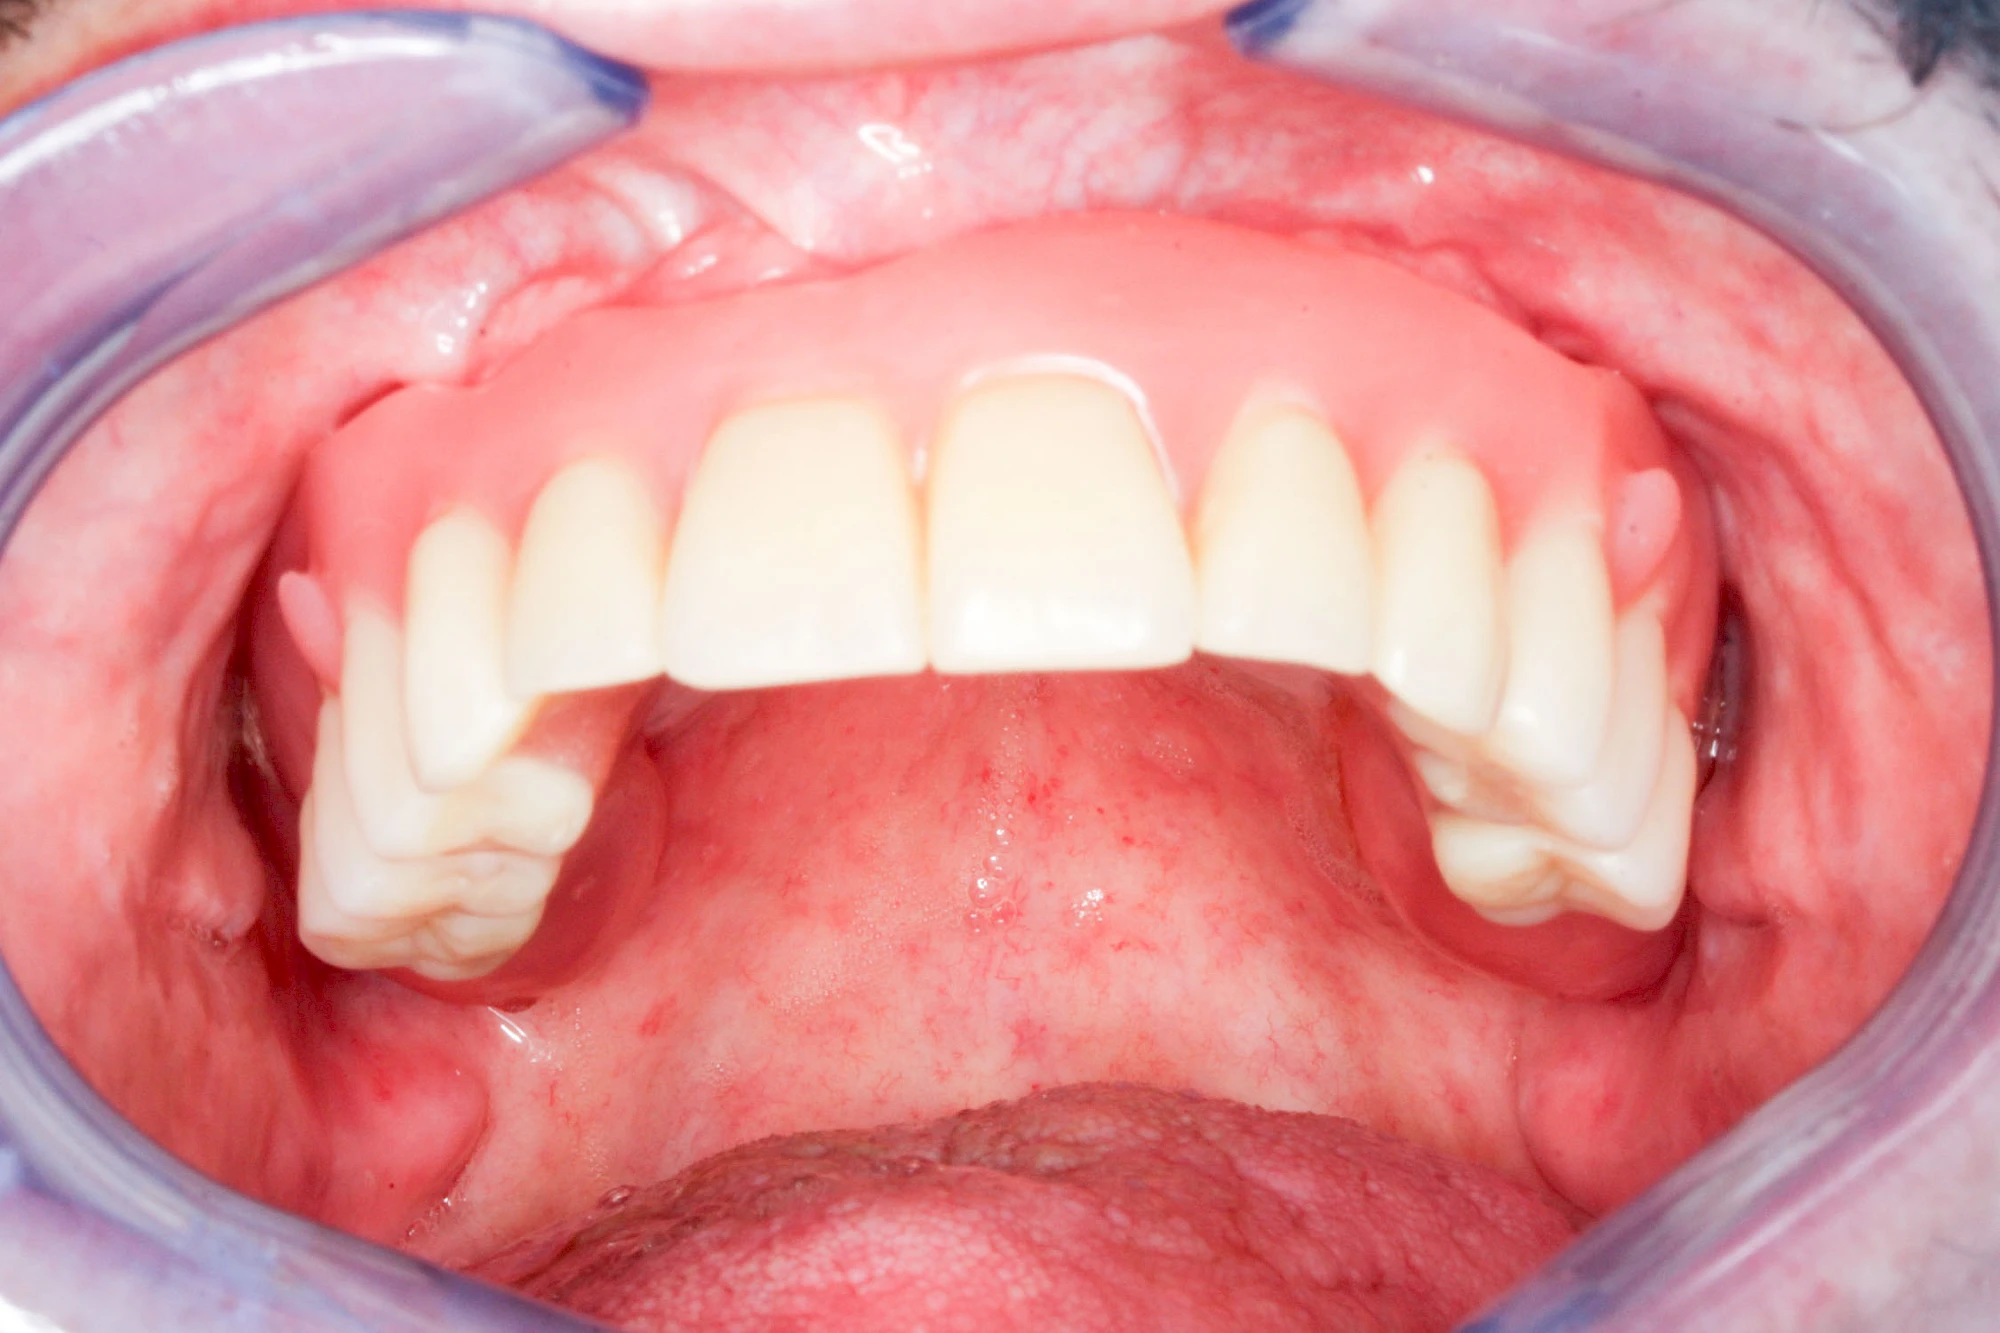

Fehlen einzelne Zähne und die Nachbarzähne sind unbeschadet oder gut zahnärztlich versorgt, werden immer häufiger Implantate gewählt, um die Lücken zu schließen. Auch bei größeren oder verteilten Lücken, wenn keine herausnehmbare Prothese gewünscht ist, werden Implantate für Kronen- bzw. Brückenversorgungen gesetzt. In Einzelfällen entscheiden sich sogar zahnlose Patienten für eine festsitzende Versorgung auf Implantaten.

Varianten zur Verankerung von festsitzendem Zahnersatz auf Implantaten